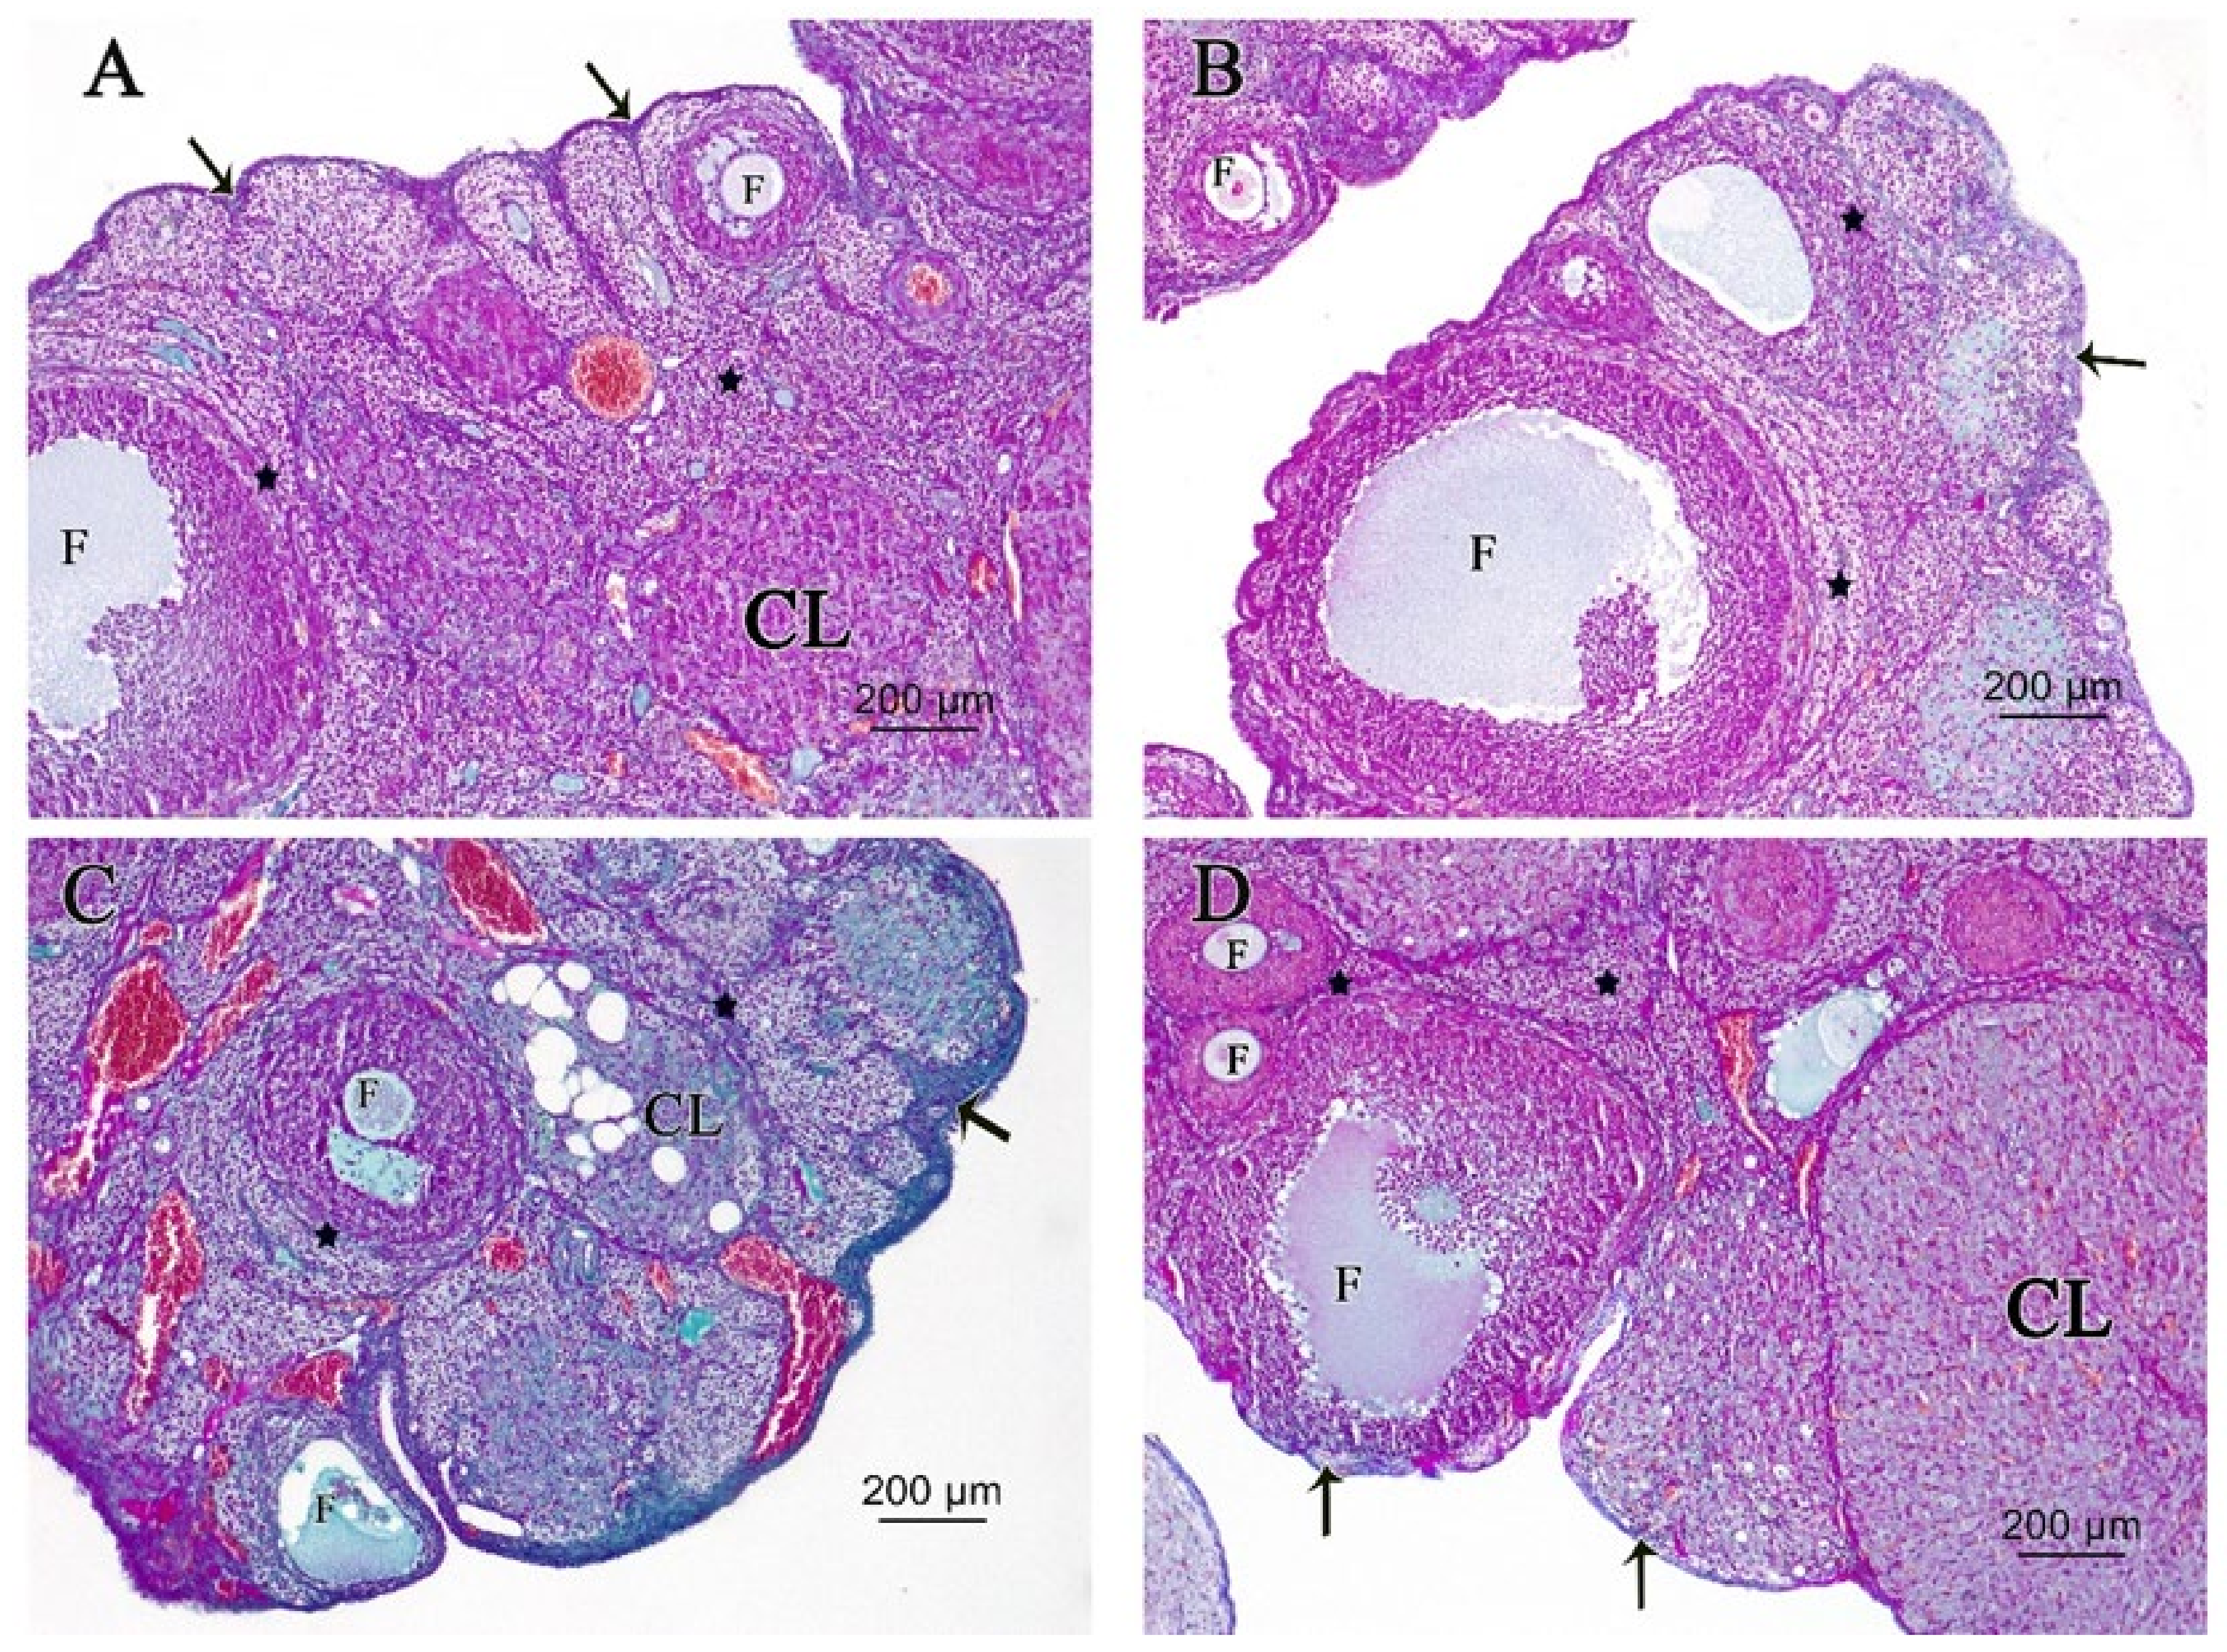

3.2.1. Ovarian Hematoxylin and Eosin (H&E)

3.2.2. Ovarian Periodic Acid-Schiff Reagent (PAS)

3.2.3. Ovarian Masson’s Trichrome (MT) Stain